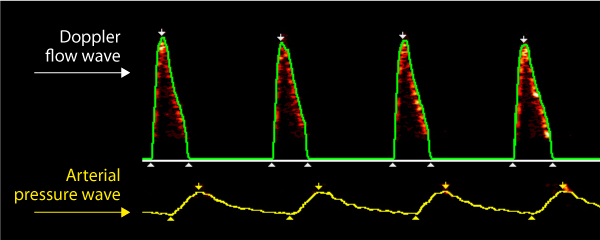

The ODM+ brings together the minimally invasive oesophageal Doppler monitoring of blood flow with a pulse pressure wave analysis (PPWA) system.

Blood Flow with Arterial Pressure

On the ODM+ monitor the arterial wave is scaled to an appropriate size for comparison with the Doppler waveform.